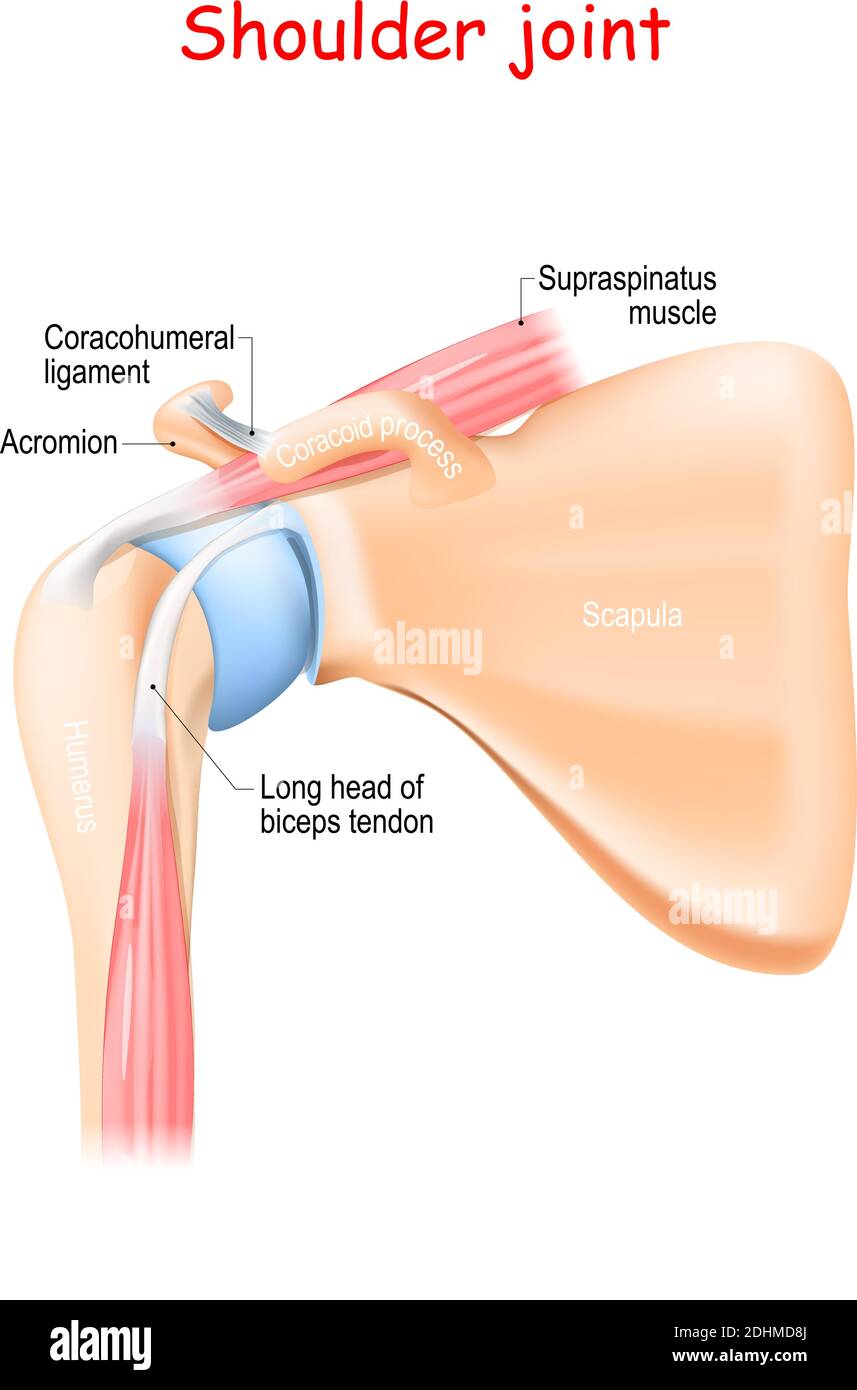

Glenohumeral ligament: анатомия и функции плечевого сустава